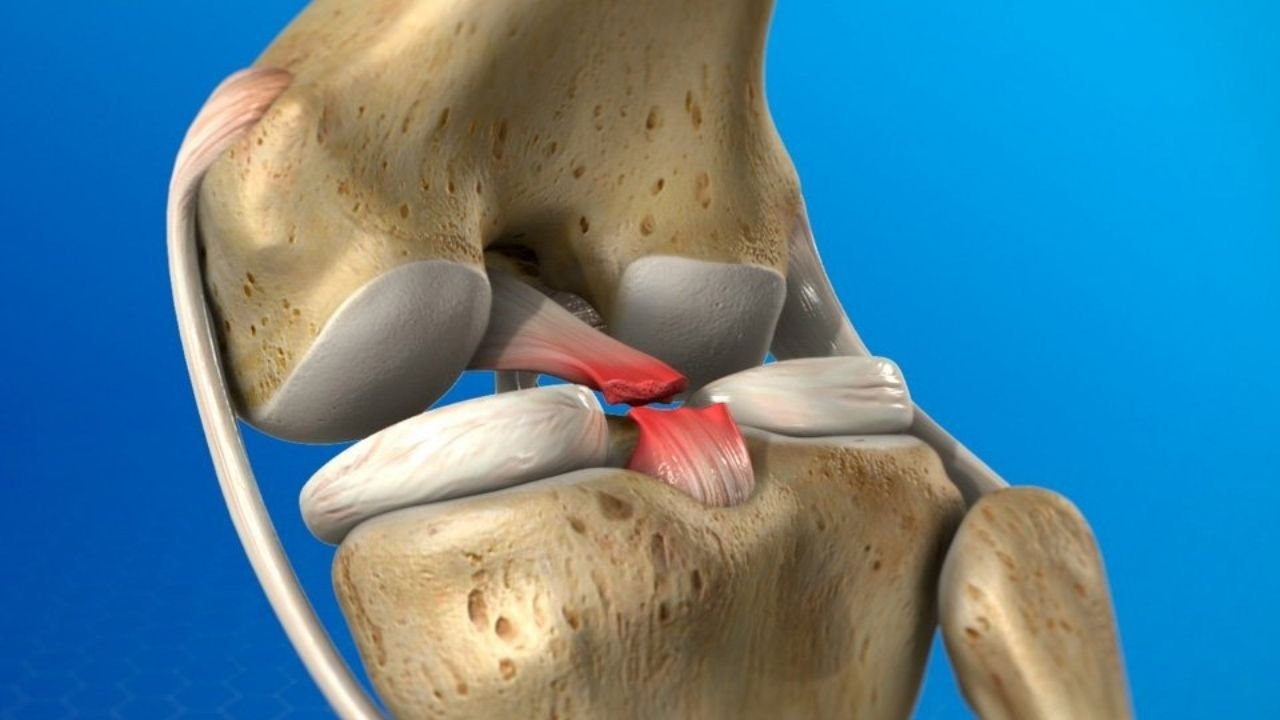

O Ligamento Cruzado Posterior (LCP) é o “irmão mais forte” do famoso LCA. Localizado na parte de trás do centro

O Ligamento Cruzado Posterior (LCP) é o “irmão mais forte” do famoso LCA. Localizado na parte de trás do centro

O Ligamento Cruzado Posterior (LCP) é o “irmão mais forte” do famoso LCA. Localizado na parte de trás do centro